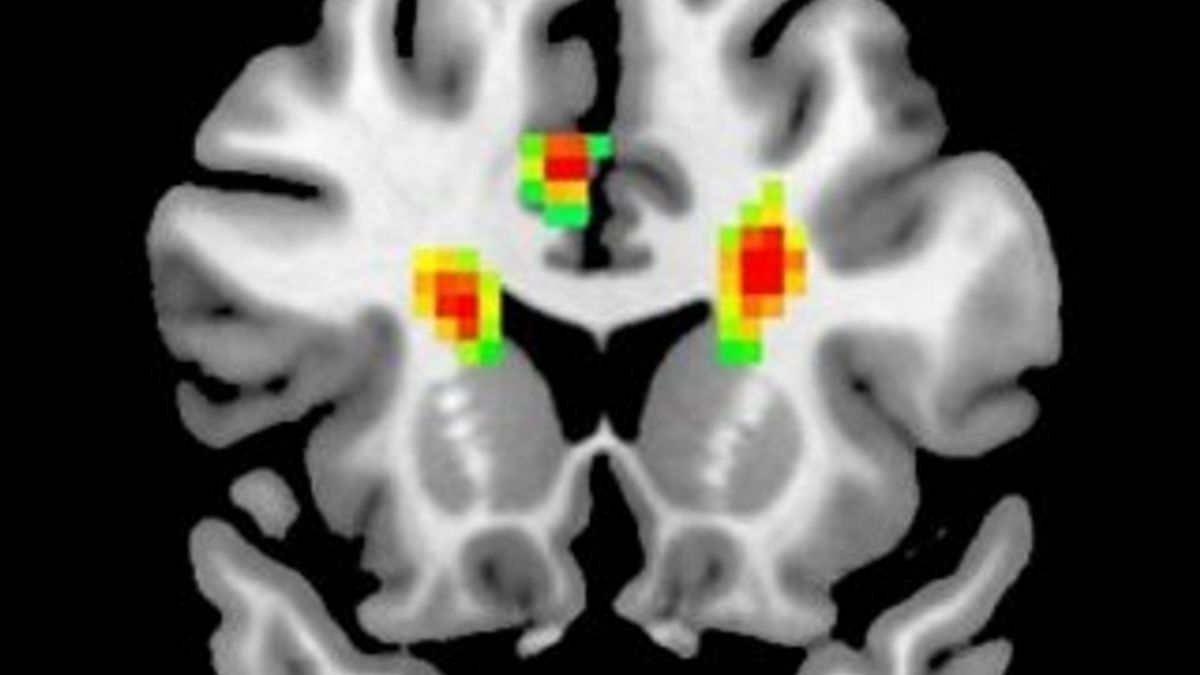

Aşık insanların beyin MR'ı çekildi(Aşık olan bir insanın beyni)

Araştırma sonucuna göre, aşıkken beynimize giden kan miktarı artıyor ve beynimizin 12 bölgesi aktif oluyor. Beynin önde gelen fonksiyonel değişiklikleriyle ilgili ilk amfirik kanıtını gözler önüne seren araştırma, aşkın insanlar üzerindeki etkilerini tam olarak açıklığa kavuşturmasa da işe bir yerlerden başlıyor.